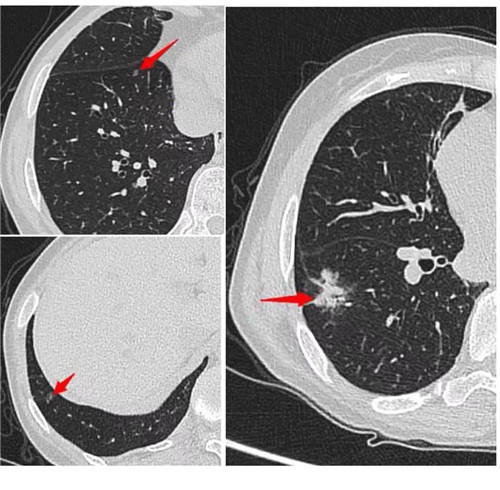

經(jīng)過術(shù)前充分評(píng)估,崔凱主任決定一次手術(shù)同期為患者切除雙肺總共六枚結(jié)節(jié)。手術(shù)團(tuán)隊(duì)?wèi)?yīng)用minics肺結(jié)節(jié)三維重建分析及術(shù)前CT引導(dǎo)下錨針穿刺定位等先進(jìn)工具,精準(zhǔn)定位患者雙肺的6枚磨玻璃結(jié)節(jié),其中最大的2cm,最小的0.6cm。

術(shù)前各項(xiàng)準(zhǔn)備完畢,崔凱主任為患者行“單孔胸腔鏡右肺下葉切除術(shù) 淋巴結(jié)清掃術(shù) 單孔胸腔鏡左肺上葉尖后段切除術(shù) 左肺下葉背段切除術(shù) 淋巴結(jié)清掃術(shù)”,一次手術(shù)成功將患者兩側(cè)肺部6枚結(jié)節(jié)全部切除,術(shù)后病理結(jié)果提示六枚結(jié)節(jié)均為早期肺癌。